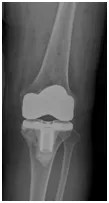

骨性关节炎早期主要累积关节表面软骨,如果在症状较轻的时候就及时干预,那么还是有很大的机会让骨性关节炎远离我们。在关节炎早期,服用NSAID类药物是可以比较明显的缓解症状,但是中晚期往往需要手术干预,休息时和夜间持续疼痛是骨关节炎患者外科手术治疗的适应症,尽管年龄不是手术治疗的禁忌症,但患者的总体情况是一个重要因素,尤其是老年骨关节炎晚期患者,往往需要行关节置换术,人工关节置换术已成为治疗关节严重病变的主要手段之一,被誉为20世纪骨科发展史重要里程碑之一。

新疆医科大学第一附属医院关节外科作为全国优势学科,每年完成髋、膝关节置换手术近2000例,其数量及难度现已位居全国领先水平,尤其在关节假体周围感染的诊断与治疗方面已达到国际领先水平,全国各地患者及国际友人常常慕名而来,且数量呈逐年递增趋势。除了丰富的临床经验和规范化的手术操作之外,关节外科还引进了美国MAKO机器人,通过机器人辅助手术定位,使人工关节假体安装更为精准,固定更为牢固,术后随访也获得了更为满意的临床疗效,始终秉承“诊对病、治好病”原则的关节外科已在国内外获得了良好的口碑。